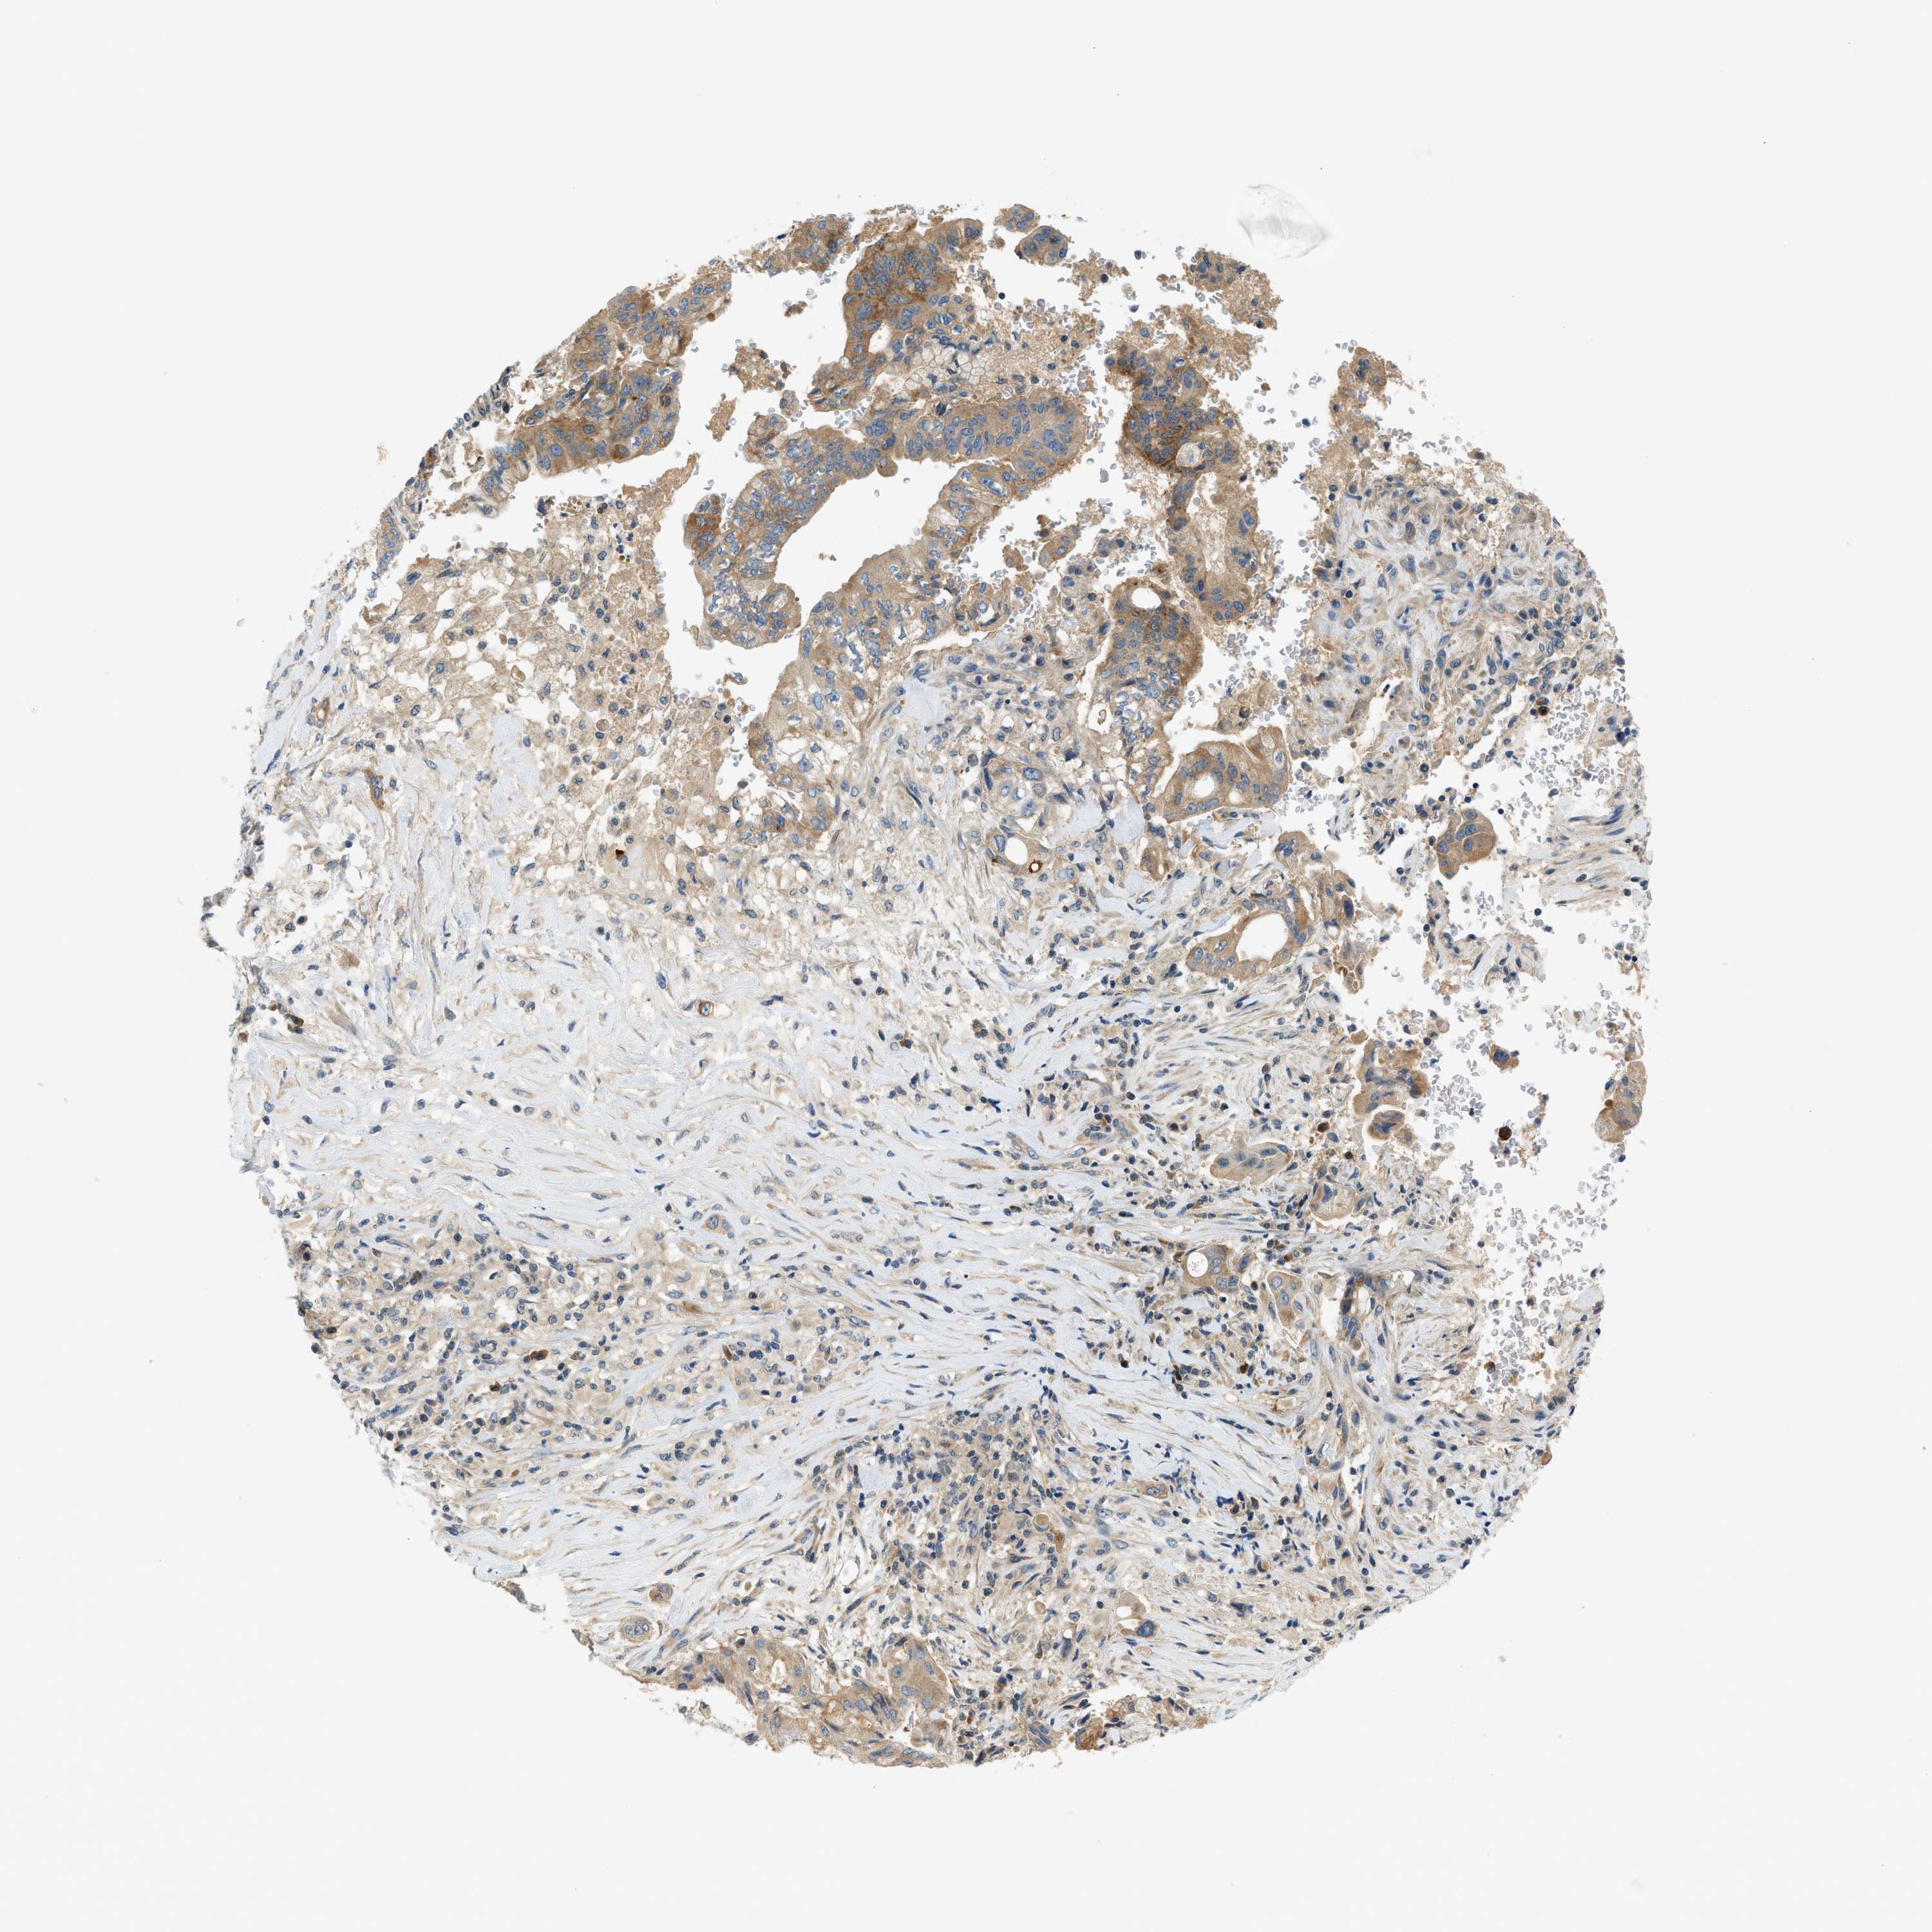

PANCREATIC CANCER - Protein expressioni

A mouse-over function shows sample information and annotation data. Click on an image to view it in a full screen mode. Samples can be filtered based on level of antibody staining by selecting one or several of the following categories: high, medium, low and not detected. The assay and annotation is described here.

Note that samples used for immunohistochemistry by the Human Protein Atlas do not correspond to samples in the TCGA dataset.

Antibody stainingi

Antibody staining in the annotated cell types in the current human tissue is reported as not detected, low, medium, or high, based on conventional immunohistochemistry profiling in selected tissues. This score is based on the combination of the staining intensity and fraction of stained cells.

Each image is clickable and will lead to virtual microscopy that enables deeper exploration of all samples and also displays staining intensity scores, fraction scores and subcellular localization as well as patient and tissue information for each sample.

Antibody HPA016049

Antibody CAB022588

Staining

High

Medium

Low

Not detected

Intensity

Strong

Moderate

Weak

Negative

Quantity

>75%

75%-25%

<25%

None

Location

Nuclear

Cytoplasmic/membranous

Cytoplasmic/membranous,nuclear

Adenocarcinoma, NOS

Adenocarcinoma, metastatic, NOS